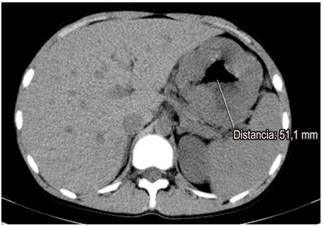

Se solicitaron paraclínicos (hemograma, albúmina, nitrogenados y uroanálisis) y se encontró anemia normocítica, normocrómica, heterogénea (hemoglobina de 11,2 g/dL), albúmina sérica de 2,8 g/dL, con creatinina de 0,8 mg/dL (normal) y uroanálisis sin proteinuria. Dado el hallazgo clínico, paraclínico y endoscópico, se decidió ampliar los estudios con tomografía axial computarizada (TAC) de abdomen, en la que se observan las paredes gástricas engrosadas con compromiso difuso y simétrico marcado de los pliegues gástricos, sin evidencia de lesiones nodulares con un espesor máximo de 53 mm (Figura 1). Se solicitó adicionalmente ultrasonografía endoscópica (USE) gástrica y desde el punto de vista endoscópico se encontraron hallazgos similares a los descritos en la EVDA; y en el tiempo ecográfico se encontró engrosamiento de la pared gástrica dependiente de la ecocapa I y II (mucosa y muscular mucosa, respectivamente), con espacios anecoicos en la ecocapa II, respetando la ecocapa III y IV (submucosa y muscular propia, respectivamente) (Figura 2).

Endoscópicamente, los pliegues de la mucosa gástrica se muestran marcadamente gruesos, lo que afecta principalmente al cuerpo y al fondo respetando el antro; el pH gástrico se incrementa debido a la pérdida de células parietales y la producción de moco espeso es copiosa, secundaria a la hiperplasia foveolar que se presenta de forma más comúnmente masiva, lo que causa a menudo el aumento en el grosor de la mucosa de 1 cm o más (en nuestro caso clínico alcanza hasta los 5 cm), lo que es una condición necesaria para el diagnóstico 5.